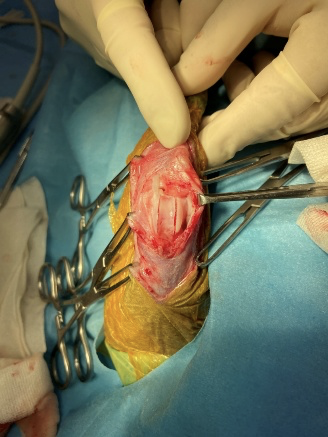

膝蓋骨内方脱臼の術中写真

滑車溝造溝術

膝蓋骨の安定性を得るために、滑車溝を造溝した所です。滑車溝を削り取ってしまうだけの造溝の場合、骨の構造が硝子軟骨から線維軟骨に置き換わり治癒することはなくなってしまいますので当院ではトンネル法という本来の滑車部分を傷付けず、内部を掘り上から本来の滑車部分を落とし込むことで溝を深くする術式を採用しています。こちらの術式の場合削り取るだけの術式より手技は難しくなりますがより自然に近い形で滑車を残すことができます。

これにより膝蓋骨が滑車から脱線しにくくなります。